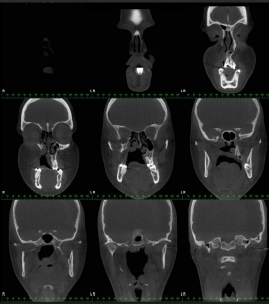

axial sections

coronal sections

saggital slicing

transaxial sections